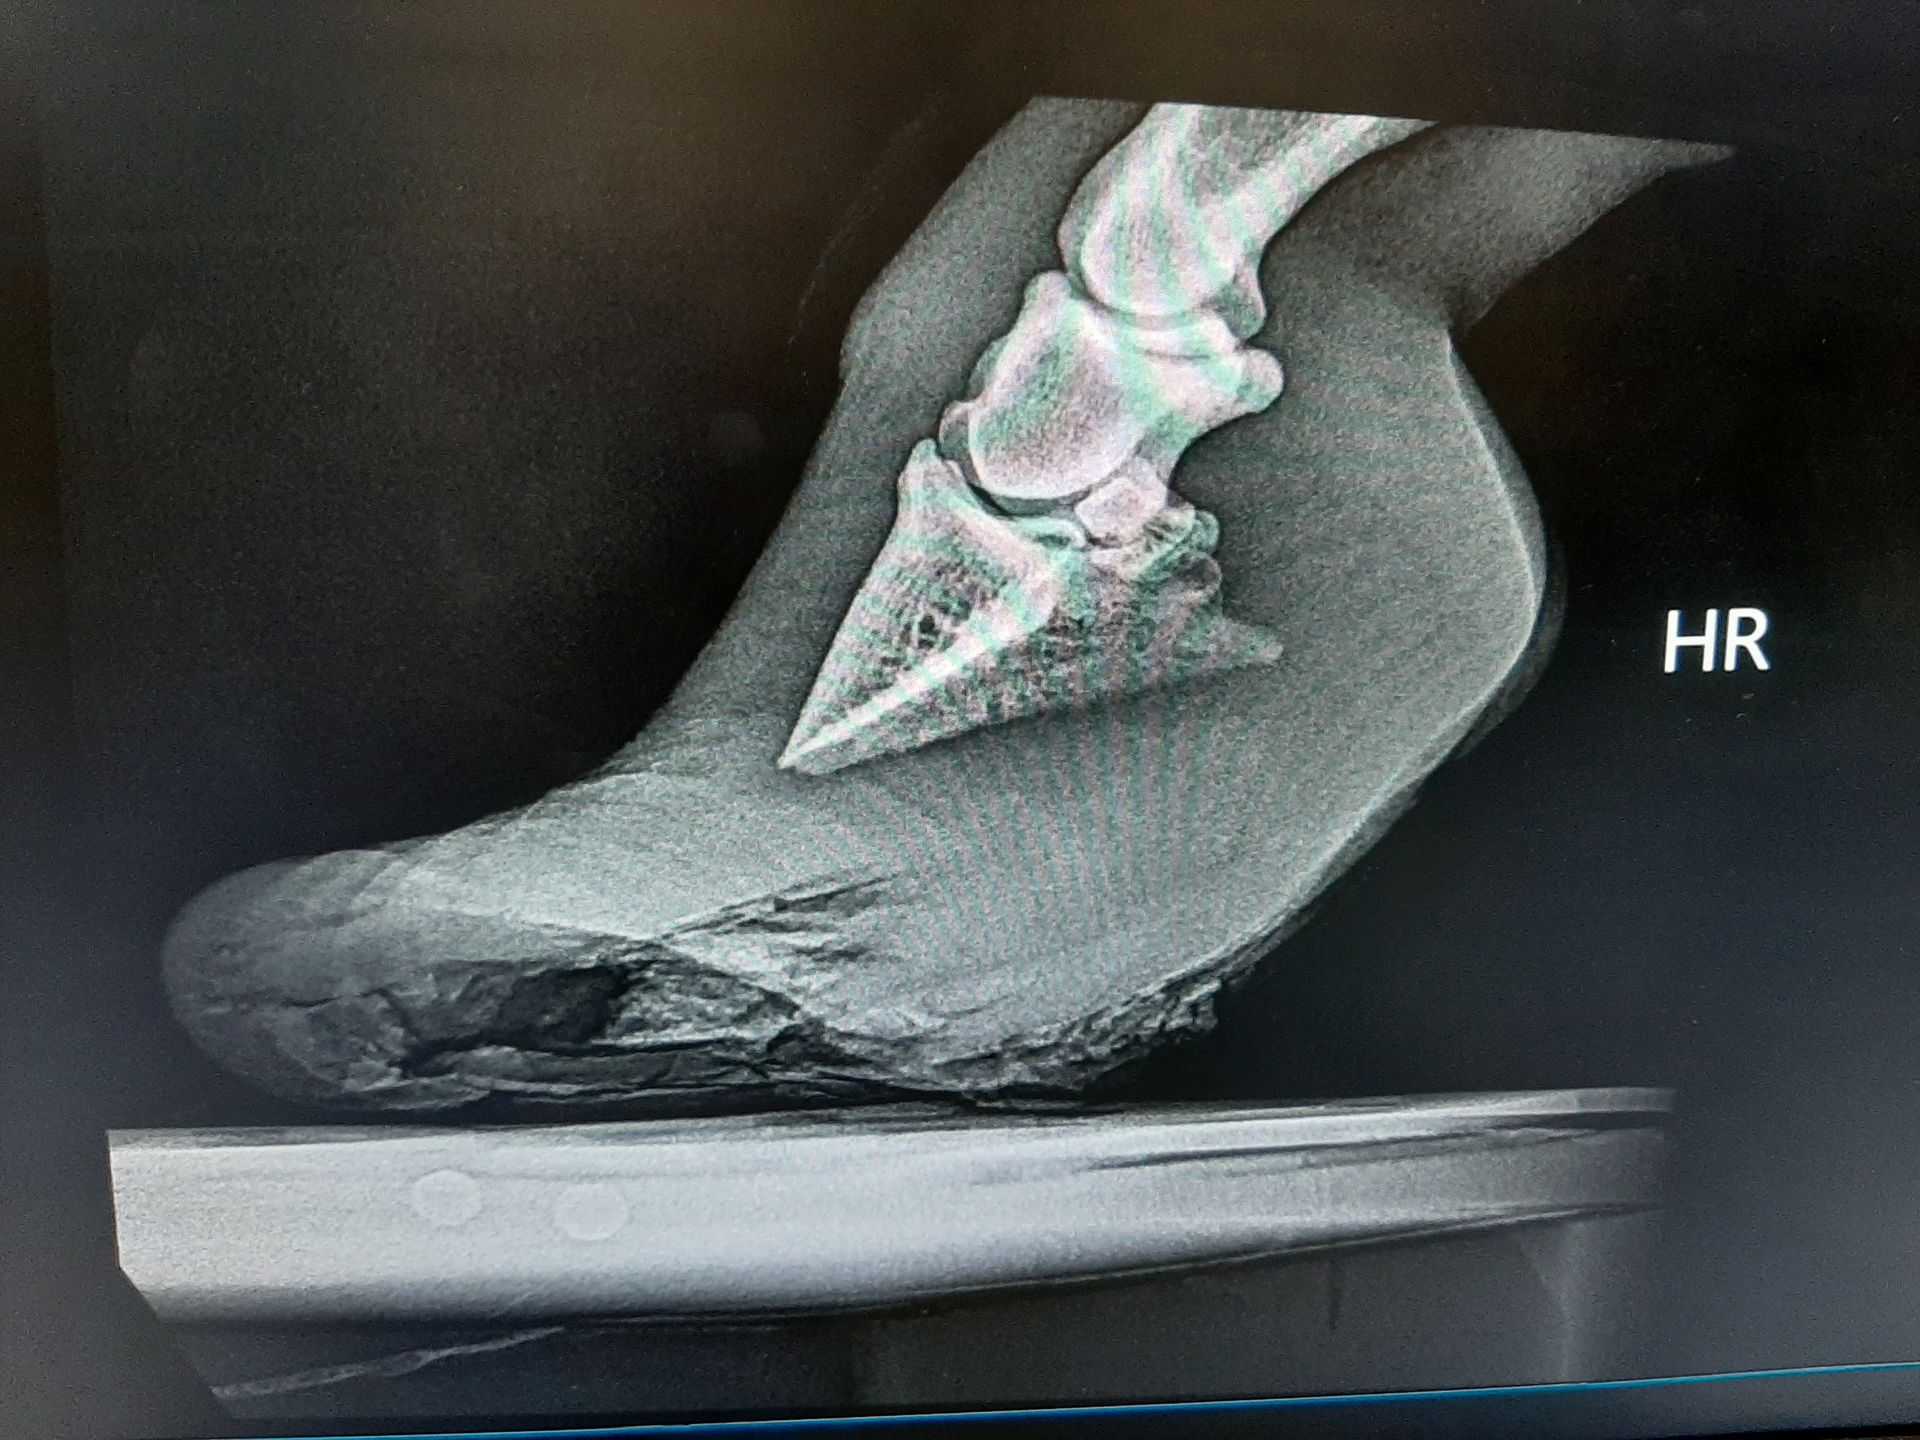

Fallbeispiel

Shetlandpony mit vernachlässigten Hufen

Behandlung: Entfernen des übermäßig gewachsenen Hufhorns

WaS war der Fall

Dieses Shetty wurde vorgestellt mit viel zu langen Hufen. Nach einer Kontrolle der Gelenken mittels Röntgenbildern wurde das überschüssige Horn entfernt.

Auf den Bildern sieht man, wie lang die Hufe sind. Nach dem Ausschneiden (Bilder fehlen leider) stand das Tier schon viel besser.